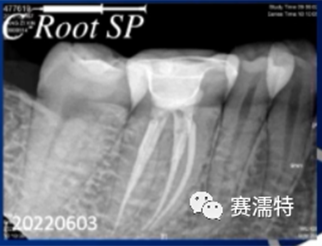

C-Root SP是預混合的、可即刻應用的、可注射的、遇水凝固的硅酸鹽類生物活性陶瓷糊劑材料,主要成分為硅酸鍶、氧化鋯、磷酸鈣、氫氧化鈣,用于根管的密封和永久充填,適合單尖法、側壓法和熱牙膠法。 C-Root SP為世界口腔醫生提供一個“鍶生物陶瓷”的新選擇! >>>

張云鳳老師案例